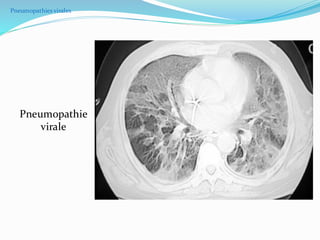

Pneumopathies virales

Opacités

alvéolaires

multiples

bilatéraux

Pneumopathie

virale